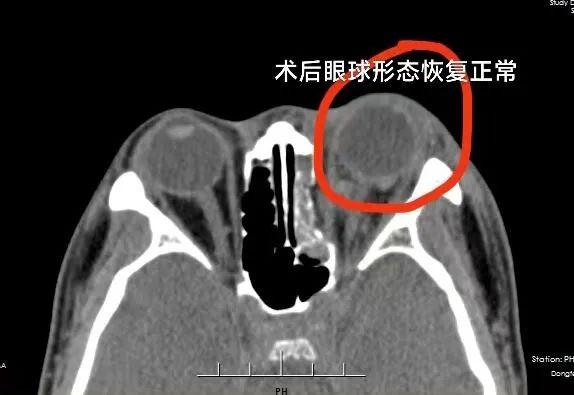

朱峰回忆,刘先生被送到医院时,眼睛受伤比较严重,经检查,他的眼镜碎片卡在了眼睛里,角膜到处血迹斑斑,眉毛也被烟花烧没了。“尽管受伤当天已经紧急做了手术,把眼睛的结构修复完整,患者能感受到些许光亮,但由于伤势较重,后期还要进行多次手术治疗。视力丧失的风险较大。”朱峰介绍。

目前,经过医院工作人员的努力,暂时保住了刘先生的眼球,想要恢复视力,后期要考虑角膜移植等方案。即便如此,也很难恢复到炸伤前的视力。